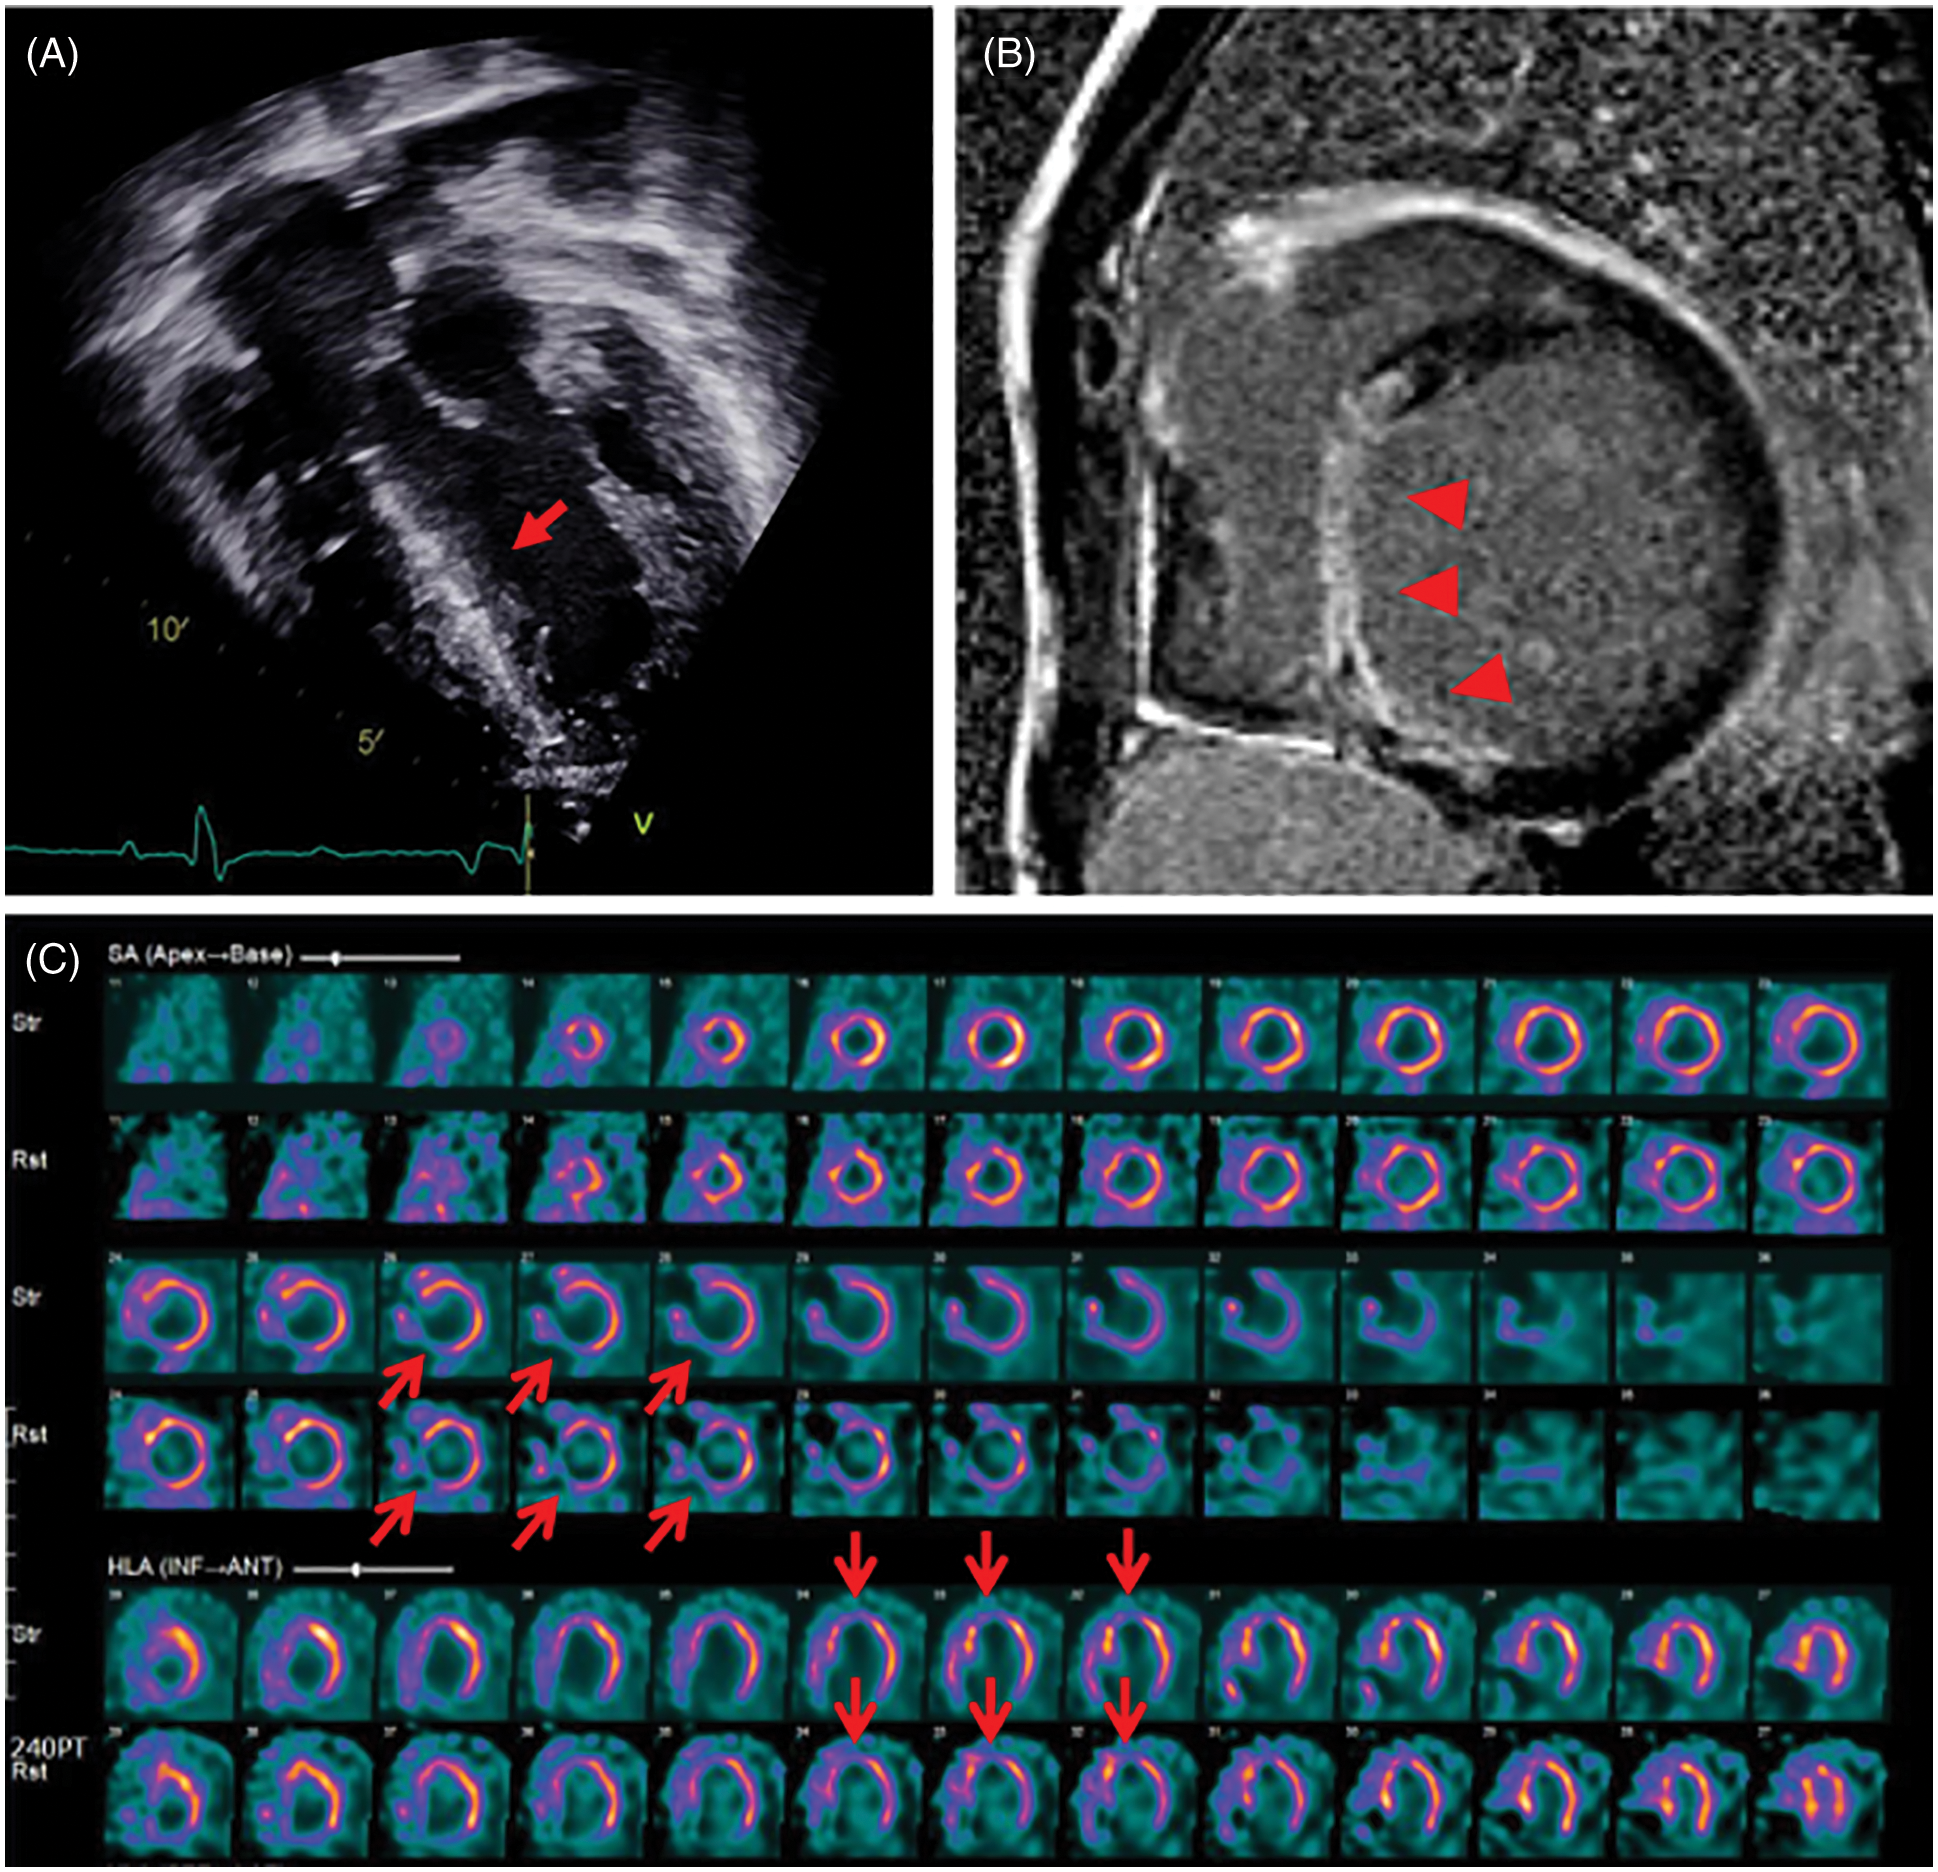

Thirteen patients showed ventricular dysfunction on echocardiography or CMR at median 3.5 years after the RVOT reconstruction surgery; however, the median time to diagnosis of CAC was 10 years after the RVOT reconstruction surgery. Among the patients with ventricular dysfunction, one patient (patient 18) who had distal LAD injury and interarterial course of RCA experienced sudden death one year after diagnosis of CAC. The last follow-up echocardiography showed mild LV dysfunction (EF 45%) with decreased apical wall motion and CMR showed delayed enhancement of LV anteroinferior wall. However, he had been observed for CAC without any medical or surgical intervention since he was in a good functional class. Unfortunately, the patient died at the age of 26 years at another hospital and the cause of death could not be found. Another patient (patient 15) was admitted due to sustained VT, 11 years after the second PVR. Echocardiography showed severe LV dysfunction (EF 20%) with increased echogenicity of the interventricular septum (Fig. 3A). CMR and myocardial SPECT suggested myocardial infarction in the LAD territory (Figs. 3B and 3C). Although coronary CTA showed normal proximal coronary arteries, ICA revealed significant mid-LAD hypoplasia and scarce septal branches. He required an implantable cardioverter-defibrillator (ICD) due to recurrent VT and persistent LV dysfunction.

Figure 3: Lately detected myocardial perfusion defect in patient 15 who underwent Rastelli procedure for double outlet right ventricle with pulmonary stenosis

Note: (A) Echocardiography showing increased echogenicity of the interventricular septum (red arrow). (B) Cardiac magnetic resonance imaging shows diffuse transmural delayed enhancement (red arrow heads) in the basal to apical inferoseptal and inferior wall. (C) Myocardial single-photon emission computed tomography shows a persistent perfusion defect on stress and rest in the mid-basal inferoseptal and basal anteroseptal wall (red open arrows).